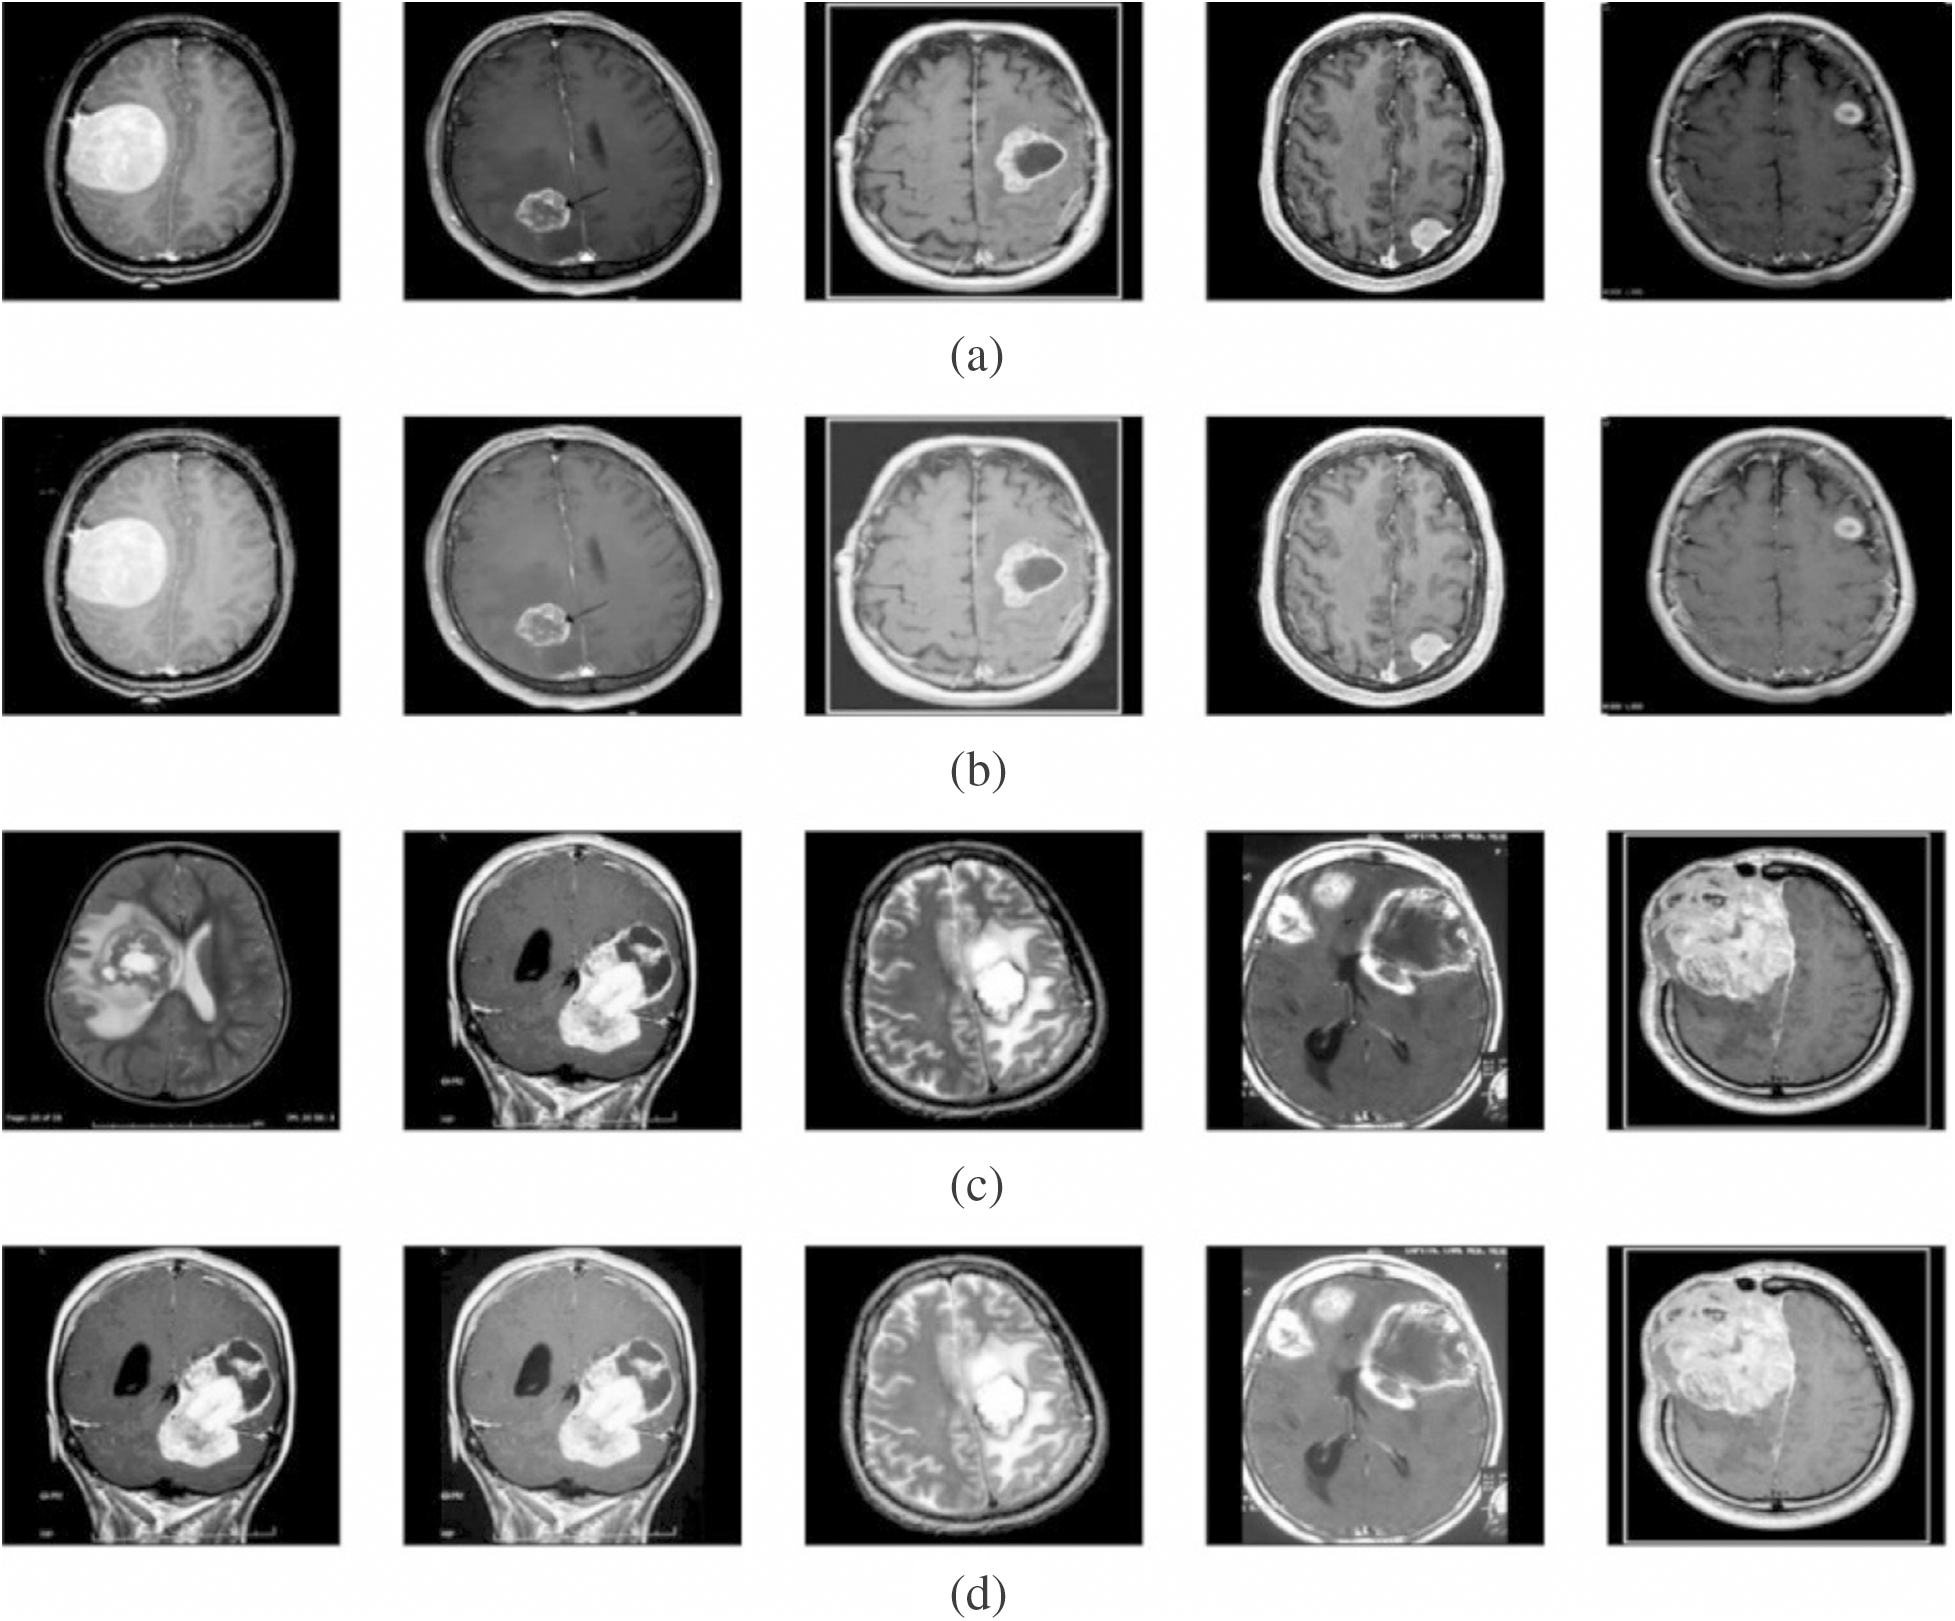

To validate the proposed model, a set of measures, namely MSE, PSNR, detection accuracy, and execution time was determined. Fig. 3 shows the outcome from the pre-processing step. The first and third rows indicate original image, whereas the corresponding contrast-enhanced images are shown in the second and fourth rows. The figure clearly states that the contrast level of the image got significantly increased by the applied model. It will be highly helpful to carry out the segmentation process.

Figure 3: Visualization of pre-processed results. (a) and (c) Original image. (b) and (d) Contrast enhanced image